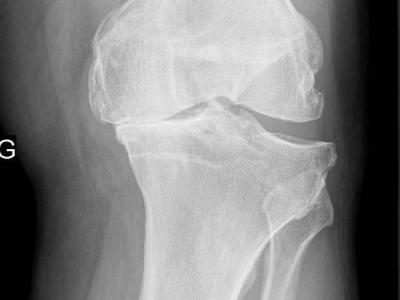

Metformin Effective in Osteoarthritis The diabetes drug metformin provided overweight/obese patients with osteoarthritis (OA) of the knee with significantly greater pain relief than did placebo in a small randomized trial, researchers said. https://t.co/7krvFFfRFC https://t.co/g1UyNjazUv